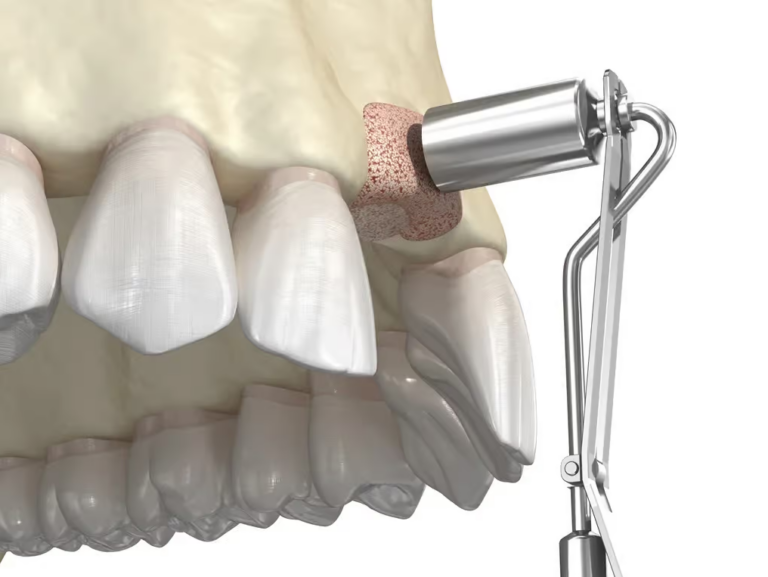

Elektrokoagulacja

Czym jest elektrokoagulacja? Elektrokoagulacja to zabieg polegający na kontrolowanym wykorzystaniu prądu elektrycznego w celu zamknięcia naczyń krwionośnych oraz usunięcia zmienionych tkanek. W stomatologii metoda ta znajduje zastosowanie przede wszystkim w chirurgii i periodontologii. Stomatolog w nowoczesnej klinika stomatologiczna Kraków wykorzystuje…